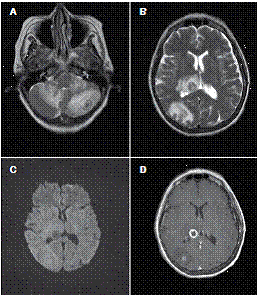

At the moment of hospitalization, the patient did not present any sign of rheumatoid arthritis activity (Clinical Diseases Activity Index: 0). A computed tomography (CT) scan of the brain was done showing a hypodense basal right lesion associated with vasogenic edema in the left frontal lobe upon which extension studies were requested. Brain magnetic resonance imaging showed supraand infratentorial lesions highly suggestive of caseous granulomas (figure 1). A chest CT showed centrilobular micronodules with soft tissue density and branched centrilobular linear densities (figure 2). Abdomino-pelvic CT showed iliac mesenteric and retroperitoneal lymphadenopathy and wall thickening of the distal ileum (figure 3), which is highly suggestive of tuberculosis as a first diagnostic possibility. Lymph node biopsy reported granulomatous lymphadenitis with acid-alcohol resistant bacilli, thus confirming the diagnosis.